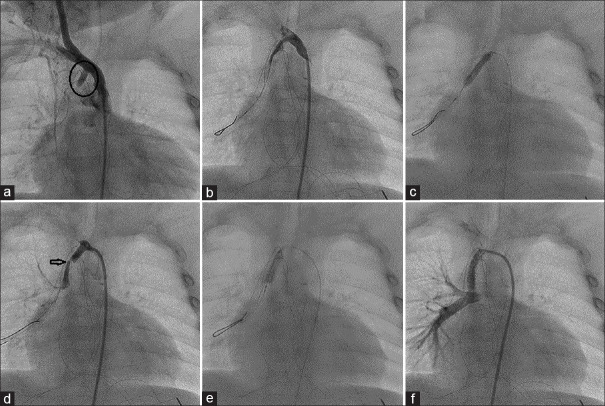

The modified Blalock-Taussig-Thomas shunt (mBTT shunt) is an effective palliation for cyanotic congenital heart diseases. However, a late obstruction of the mBTT shunt may present as a life-threatening complication. In this setting, a redo-surgery or a transcatheter recanalization is necessary to restore adequate pulmonary blood flow. We report three cases of transcatheter recanalization and stenting of a completely obstructed mBTT shunt, highlighting the tips and tricks of the percutaneous approach.

Abstract Image